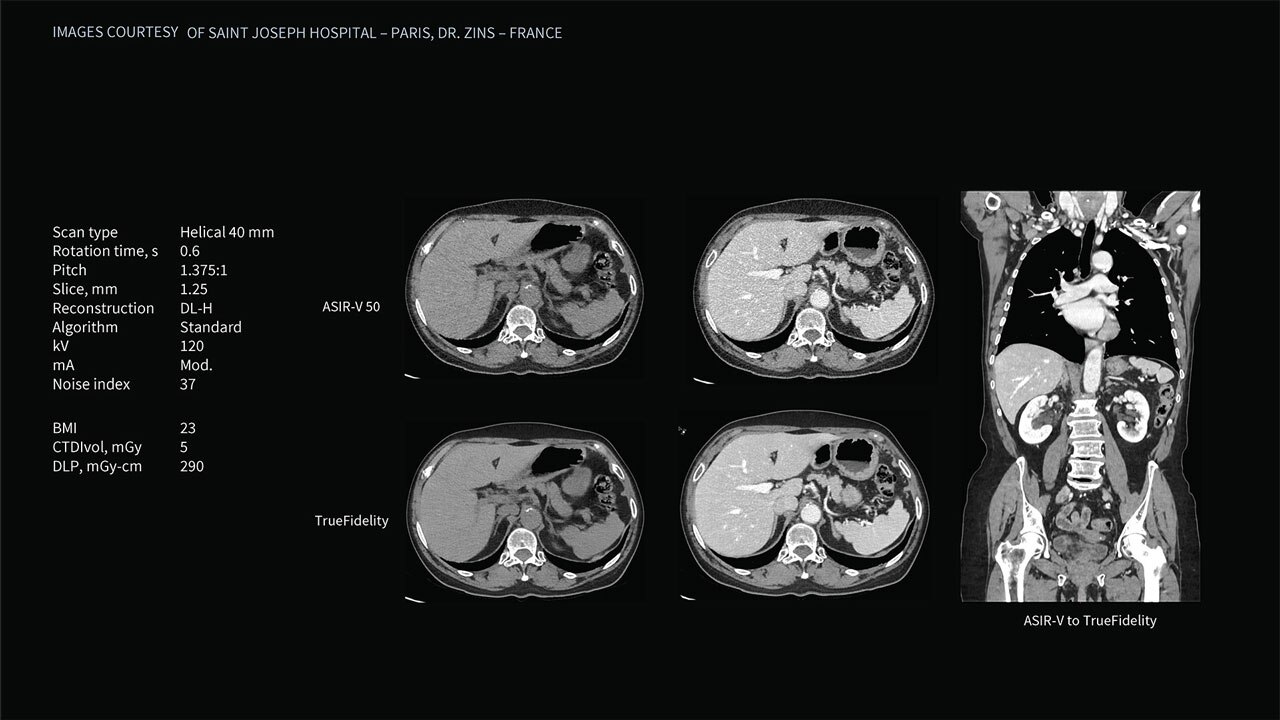

Deep learning image reconstruction, higher special resolution at 0.23 mm